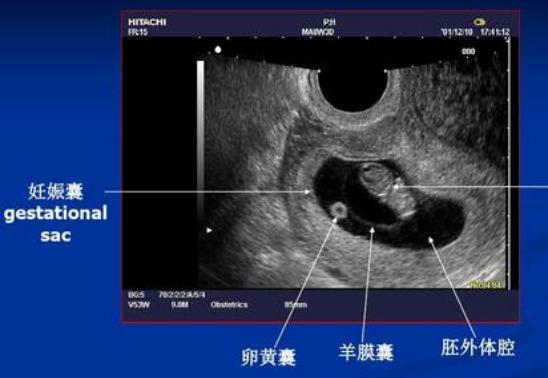

① 第一次B超:刚怀孕,明确孕囊着床的位置

有的医生会在刚怀孕时会给做阴超(因为经腹B超还看不到),目的是为了明确孕囊着床的位置,从而判断是宫内孕还是宫外孕,这是决定是否可以继续妊娠的关键;但也有些医生不建议做,觉得没多大必要。

到了怀孕7周左右,通过B超检查,可以显示宫腔内的孕囊(胎芽)以及原始心管搏动(胎心),而大部分孕妈都会做这个B超。若是刚怀孕时没做B超,那这个B超就算第一次B超。